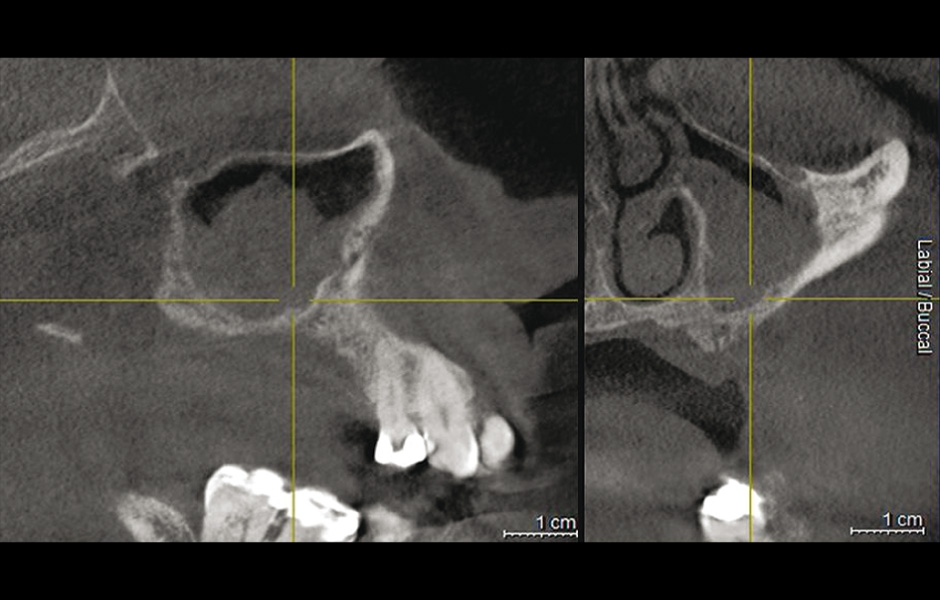

Obr. 6: CBCT po 10 letech od augmentace a zavedení implantátů ukazuje oblast bez recidivy.

Obr. 7: CBCT: částečné zastínění pravého maxilárního sinu po neúspěšném sinus liftu s bovinním kostním náhradním materiálem.

Do studie bylo zařazeno 10 pacientů s aspergilózou maxilárního sinu. U všech pacientů byl na panoramatických snímcích i na CBCT patrný radiopakní stín. CBCT navíc ukázalo, že čelistní dutina byla kompletně vyplněna homogenní patologickou masou. Chirurgická léčba sinu byla provedena za antibiotické profylaxe (Amoxicillin 2 g/den po dobu 7 dní) a intravenózní sedace (Midazolam). Kostní okénko bylo vytvořeno mikropilkou (DENTSPLY Implants), umožnilo bezpečný přístup do sinu. Po odklopení separovaného kostního fragmentu byla aspergilóza spolu s cizorodým materiálem kompletně odstraněna a dutina vypláchnuta peroxidem vodíku (H₂O₂ 3 %). Pro dodatečnou dezinfekci byla použita fotodynamická dekontaminace laserem HELBO (HELBO, Bredent Medical GmbH). Na závěr zákroku byla kostěná lamela vrácena zpět jako biologický uzávěr sinu a fixována resorbovatelnými stehy. Histopatologické vyšetření ve všech případech potvrdilo infekci aspergilózou. Po třech měsících, kdy CBCT potvrdilo nepřítomnost sinusové patologie a průchodné ostium, byla provedena augmentace kosti. Kostní bloky byly odebrány z retromolárové oblasti mandibuly a přeneseny ve 3D konfiguraci podle split-bone block techniky v kombinaci se sinus liftem. Sinus byl augmentován autologní kostí a biomateriálem (FRIOS Algipore®, DENTSPLY Implants) vrstvenou technikou. Po dalších třech měsících byly do augmentované oblasti zavedeny implantáty. O další tři měsíce později byly implantáty odhaleny a následně byla zhotovena definitivní protetická náhrada.“